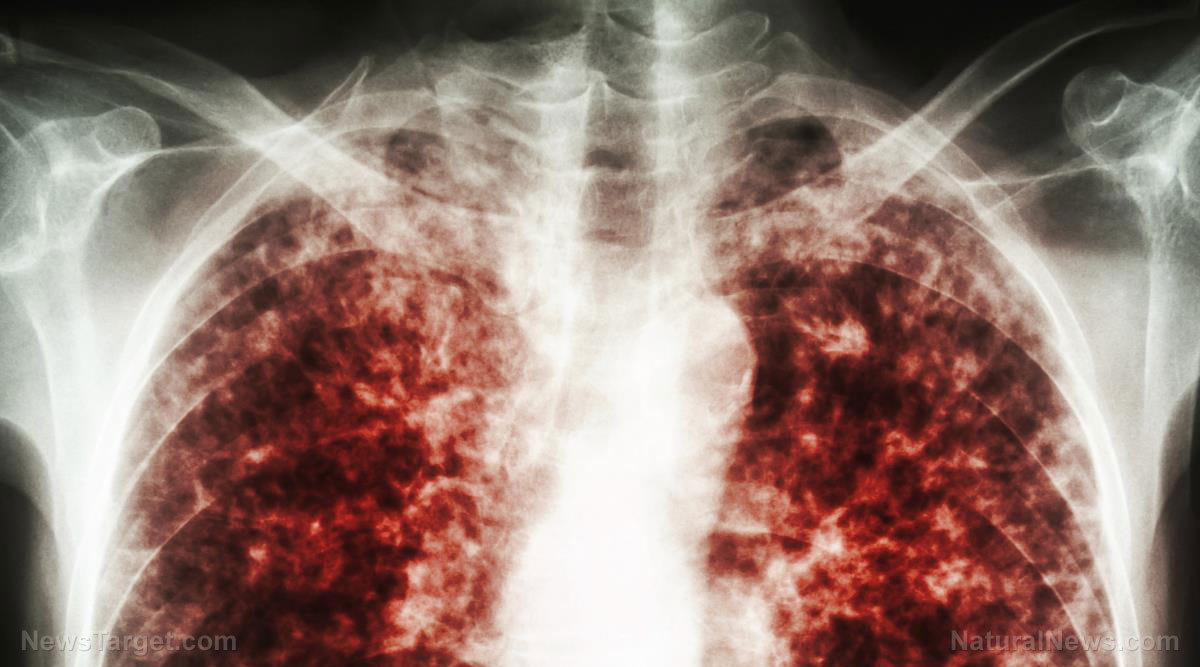

Denmark seeing surge in same “white lung syndrome” pneumonia supposedly found in China

Mycoplasma pneumoniae, a bacterial infection known to cause the disease known as "white lung syndrome" pneumonia that does not respond to most antibiotics, has reportedly reached "epidemic" levels of infection in Denmark, prompting fresh concerns about a new disease outbreak.

Beijing is saying much the same thing about what it is calling a "mystery" wave of pneumonia that has arrived just in time for the winter season. China's mystery pneumonia is characterized by inflammation of the lungs, particularly in children.